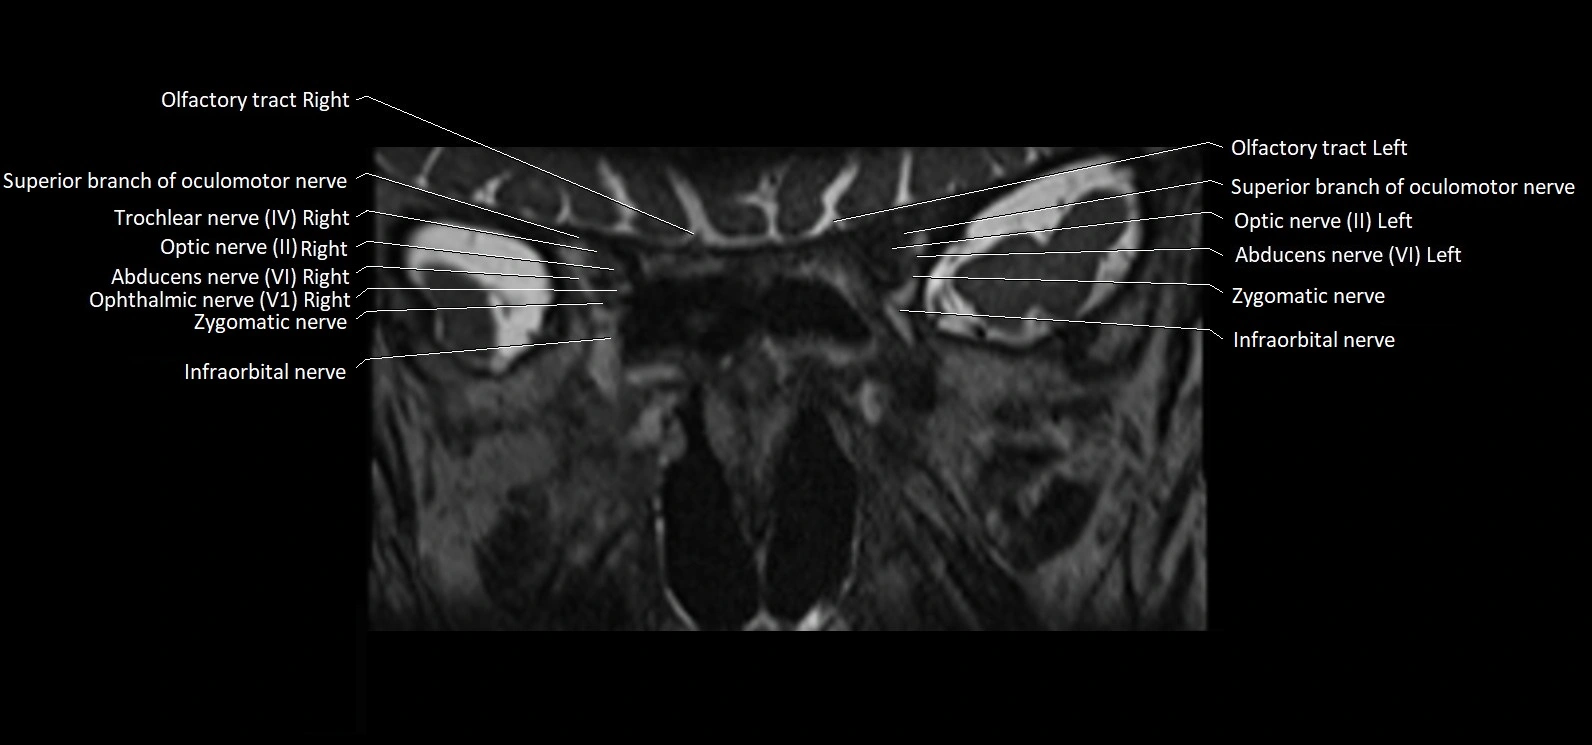

MRI Appearance

• The abducens nerve is a small, thin, linear structure

• Best visualized on high-resolution T2-weighted 3D MRI sequences (e.g., FIESTA or CISS)

• Seen as a hypointense (dark) line running from the brainstem at the pontomedullary junction, traversing the prepontine cistern, and entering Dorello’s canal under the petrosphenoidal ligament, then into the cavernous sinus, and finally the orbit

• May be challenging to visualize in standard MRI due to its small size

• Pathology may be inferred by absence, displacement, or enhancement of the nerve